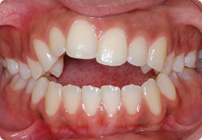

Femenino

Antes

Despues

Caso: 20 años

Adulto: Clase II,

Mordida Abierta Anterior

Sin extracción

4 series de alambres:

.016″, .022″, .0215″ x .028″, .019″ x .025″ Trenzado;

Elásticos en cajas

Triangulares TP Rosa, Verde, Azul

Retenedores: Inferior Fijo

Tiempo de tratamiento: 16 Visitas